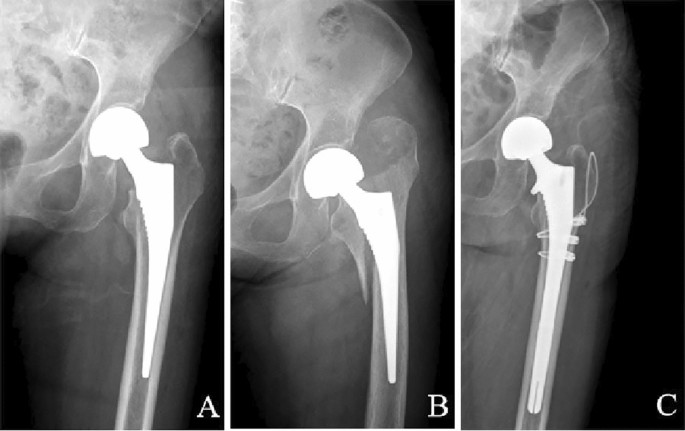

Two treatment methods were adopted. Longer stem revision and internal fixation (LSRIF) with cables was applied in 24 cases (Figs. 1 and 2). Open reduction and internal fixation (ORIF) with cables was done in four cases (Fig. 3). The choice of surgical treatment was based on the patient’s physical condition. The standard treatment was LSRIF, while ORIF was chosen if the patient was in poor condition and could not tolerate LSRIF.

Postoperative pseudo ALT fractures were seen in 28 patients (7 males [25% and 21 females [75%]). The age of the patients at surgery was 73.7 (range: 52–92) years. Of the cases, 27 (96.43%) occurred with non-cemented stems, and 1 (3.57%) with cemented stems (Fig. 4). The basic patient data are summarised in Table 1.

Case 1, an 82-year-old man underwent left hemi-arthroplasty with a cemented stem because of a left femoral neck fracture. (A–B) Two intraoperative radiographs taken with a C-arm machine. (C) After a fall, the continuity of the left medial femoral cortex was interrupted on an anterior–posterior radiograph. (D) Postoperative anterior–posterior radiograph after longer stem revision and internal fixation with cables.